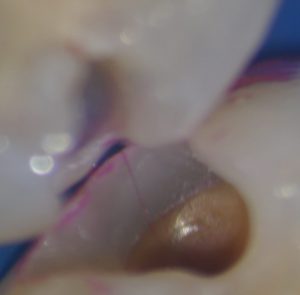

齲窩を開口するとがっつり虫歯。

ある程度虫歯を除去し、虫歯を染めると、線上に染まります。

出来れば辺縁隆線を保存したかったのですが、意外と虫歯が大きく、ボコッと行ってしまいました。

実はこの症例、エナメル質の虫歯、マイクロ下でも見えなかったんです。

なのにこんなに大きな虫歯が・・・

クラックから菌が入ってしまうんですね・・・